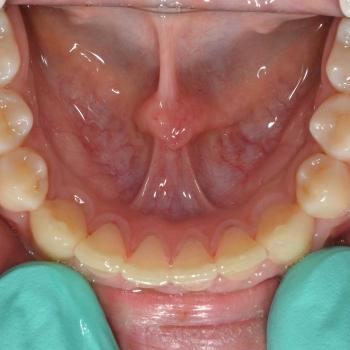

Nándi és édesanyja esztétikai okokból, a kiálló szemfogak és a réses felső metszőfogak miatt kerestek fel. Az első konzultáció alkalmával ezen túlmenően komoly helytöbbletet fedeztünk fel az alsó fogívben, illetve mélyharapást és a szemfogak területén Class II-es harapási eltérést tapasztaltunk.

A kezelési terv természetesen az összes eltérést figyelembe vette és ennek megfelelően a problémák megoldásához rögzített fogszabályozót, EVA-platte harapásemelőt és különböző intermaxilláris gumikat használtunk.

Nándi kitartásának és az előre megtervezett lépéseknek hála tökéletes funkciót és esztétikai végeredmény értünk el.

A kezelés teljes időtartama: 2 év 6 hónap